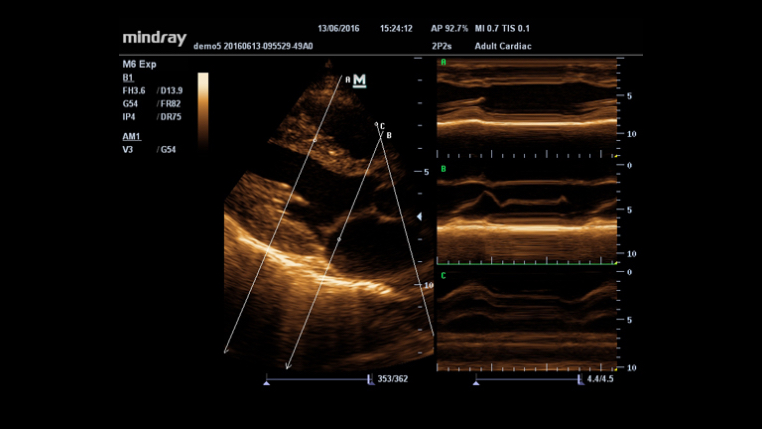

?? ? ? ???? ???? B ??, ?? ??, PW ??? ?? ?? ?? ?? ???? ??? ? ????.